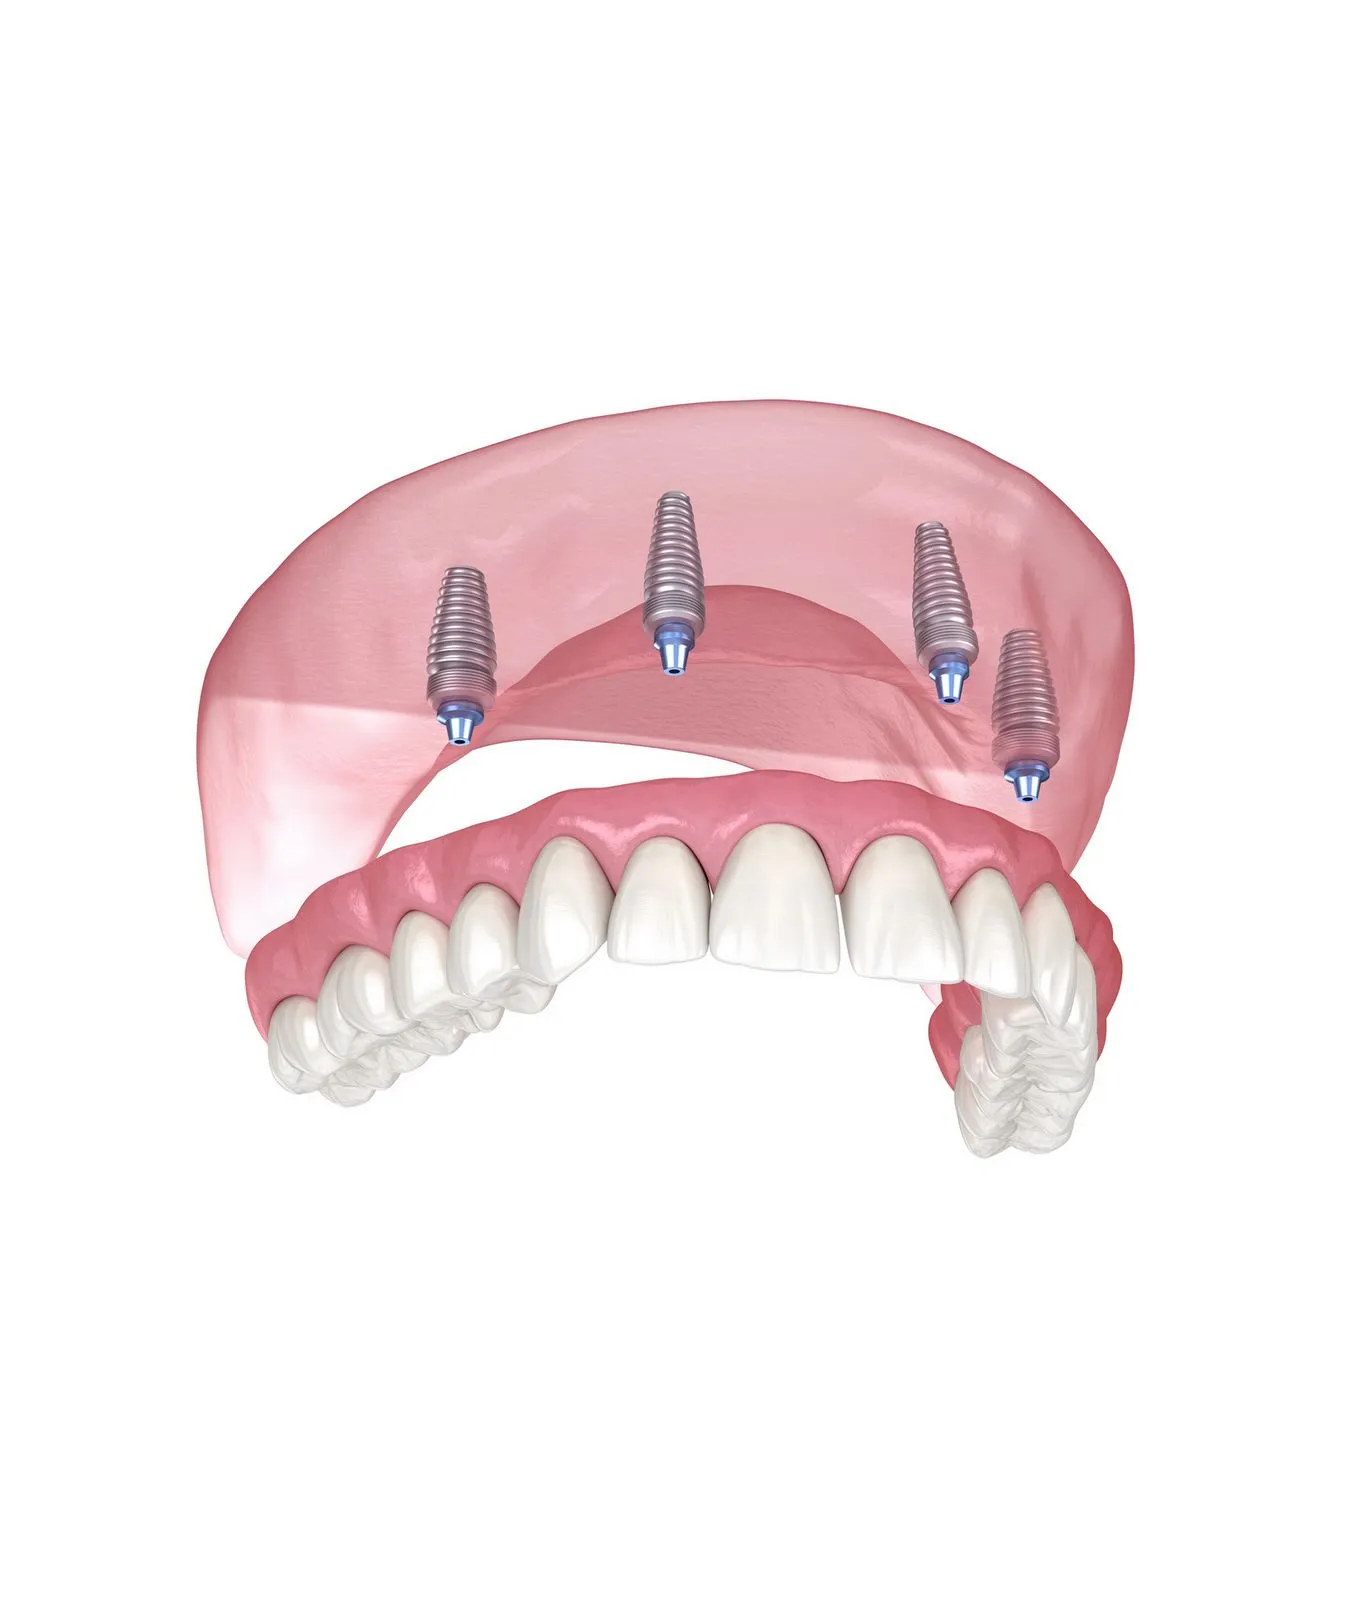

All-on-4 & All-on-6 implantati

Omogućujemo potpuno fiksne protetske nadomjestke za bezube pacijente pomoću inovativnih implantoloških rješenja koja vraćaju punu funkcionalnost, stabilnost i prirodan izgled osmijeha — često već u jednom danu.

All-on-4® i All-on-6 koncepti omogućuju trajno rješenje za pacijente koji su izgubili sve zube ili imaju zube loše prognoze. Na samo četiri ili šest strateški postavljenih implantata izrađuje se potpuno fiksni most.

All-on-4® koncept, razvijen od strane Nobel Biocare®, omogućuje ugradnju implantata pod posebnim kutovima kako bi se maksimalno iskoristila postojeća kost, čak i kod izražene atrofije čeljusti.

All-on-6 koncept koristi se kada anatomski uvjeti dopuštaju dodatnu stabilnost pomoću šest implantata, čime se dodatno povećava nosivost i dugoročna sigurnost protetskog rješenja.

All-on-4®

Fiksni most na četiri implantata, idealan kod izraženog gubitka kosti.

All-on-6

Dodatna stabilnost pomoću šest implantata kod povoljnijih anatomskih uvjeta.